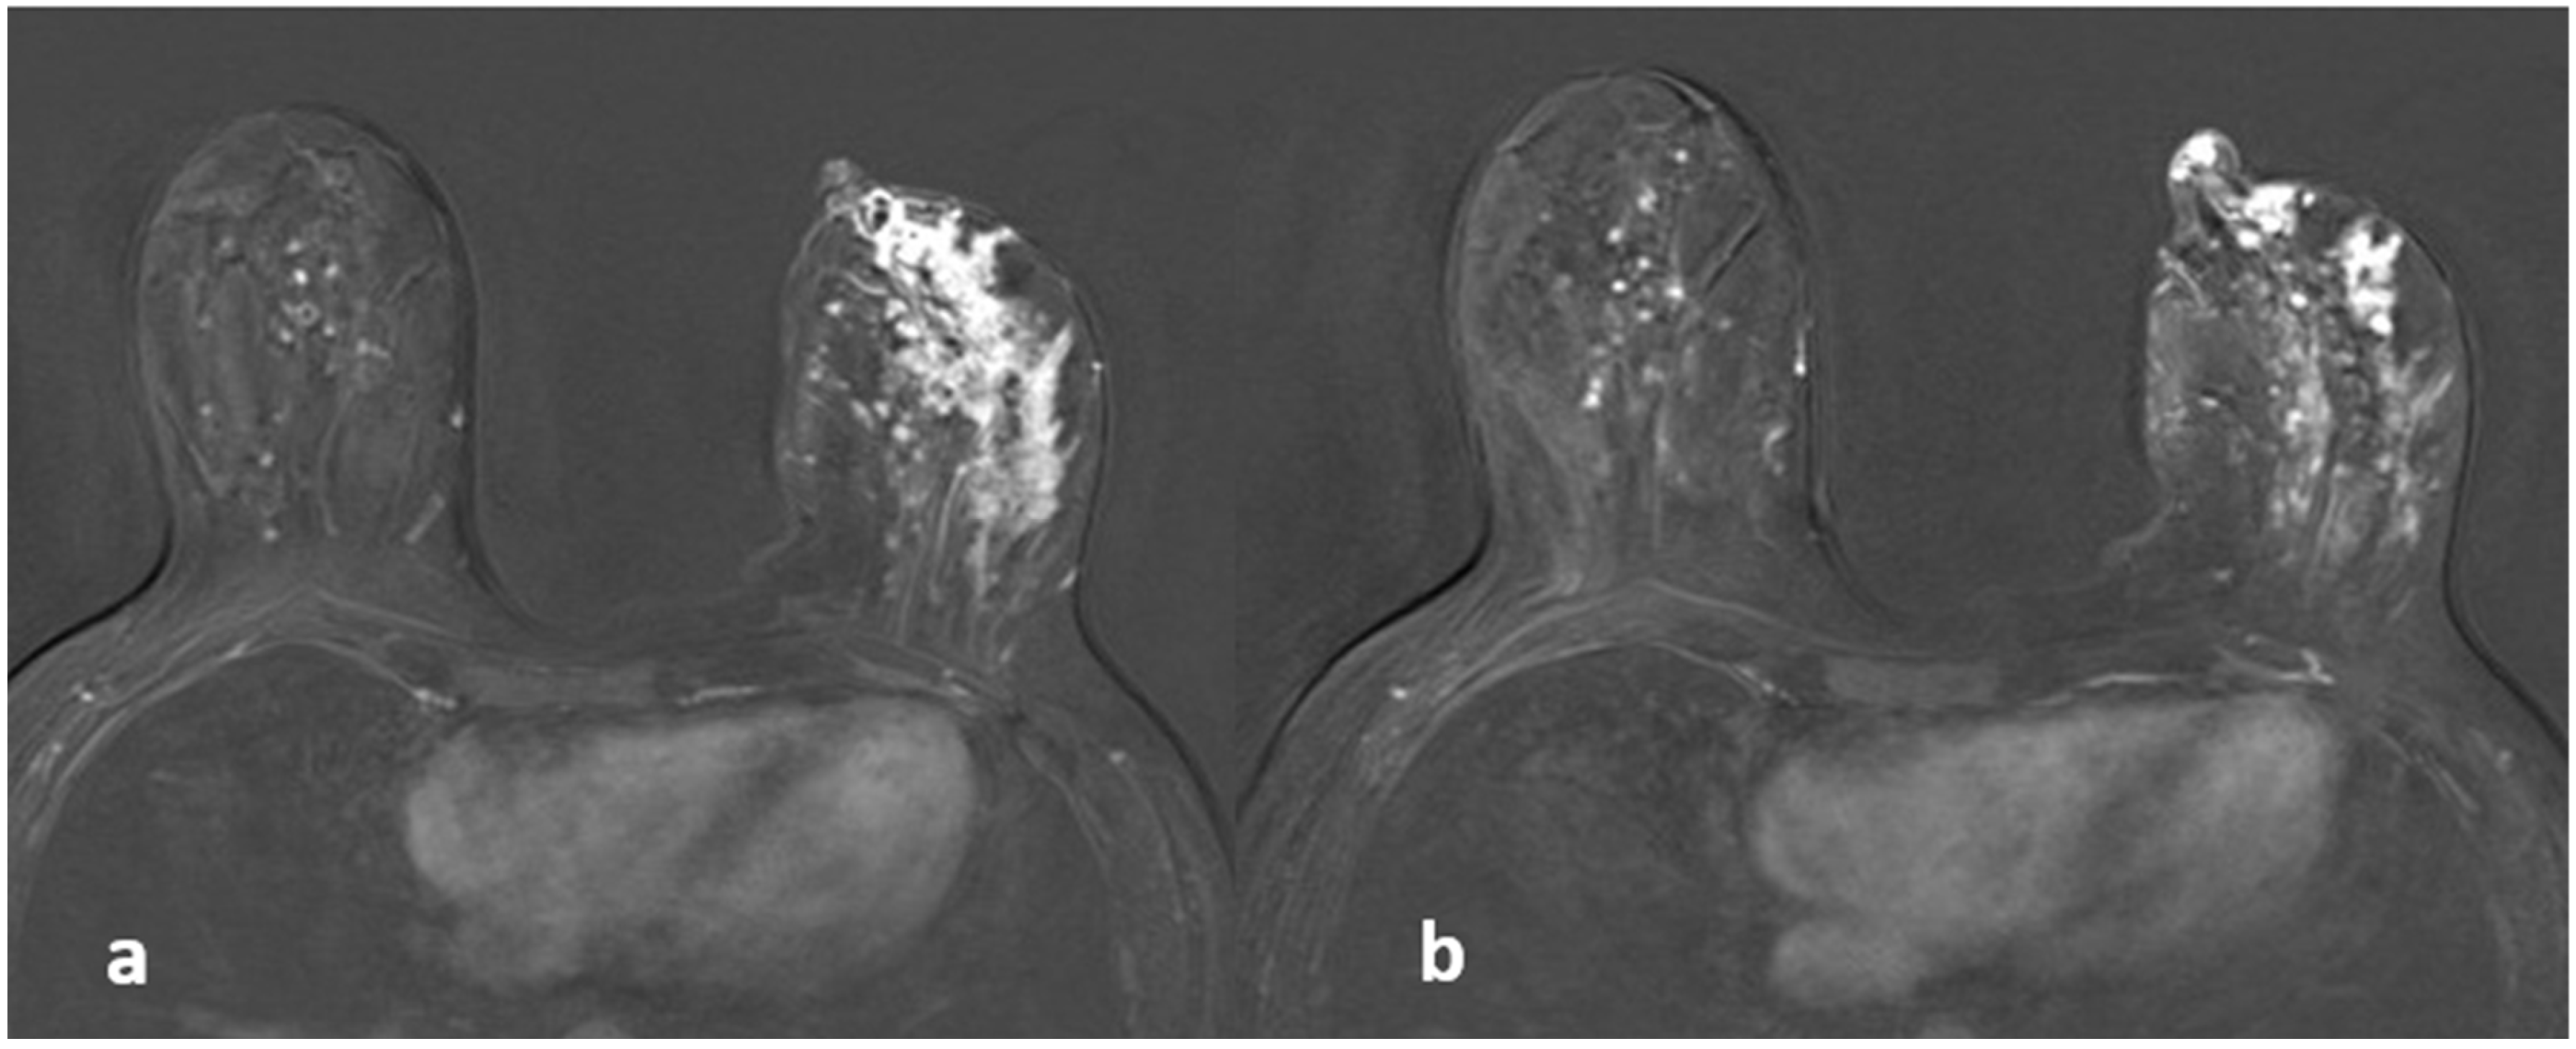

3.2. Contrast-Enhanced Images

3.3. Overall Evaluation